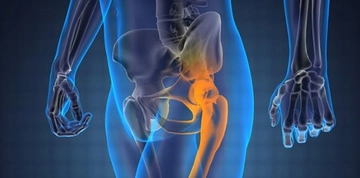

Kireçlenme Nedir?Kireçlenme, tıpta "osteoartrit" olarak adlandırılan bir durumdur ve eklemlerde kireç veya kalsiyum birikmesi sonucu oluşan dejeneratif bir hastalıktır. Bu durum, eklem kıkırdağının aşınmasına ve eklem yüzeylerinin sertleşmesine yol açarak, hareket kısıtlılığı ve ağrıya neden olur. Kireçlenme, genellikle yaşla birlikte artış gösterir ancak genetik, obezite ve eklem yaralanmaları gibi birçok faktör de bu durumu tetikleyebilir. Kireçlenmenin BelirtileriKireçlenme belirtileri genellikle yavaş bir şekilde gelişir ve zamanla şiddetlenebilir. Aşağıdaki belirtiler, kireçlenme ile ilişkili yaygın bulgulardır: